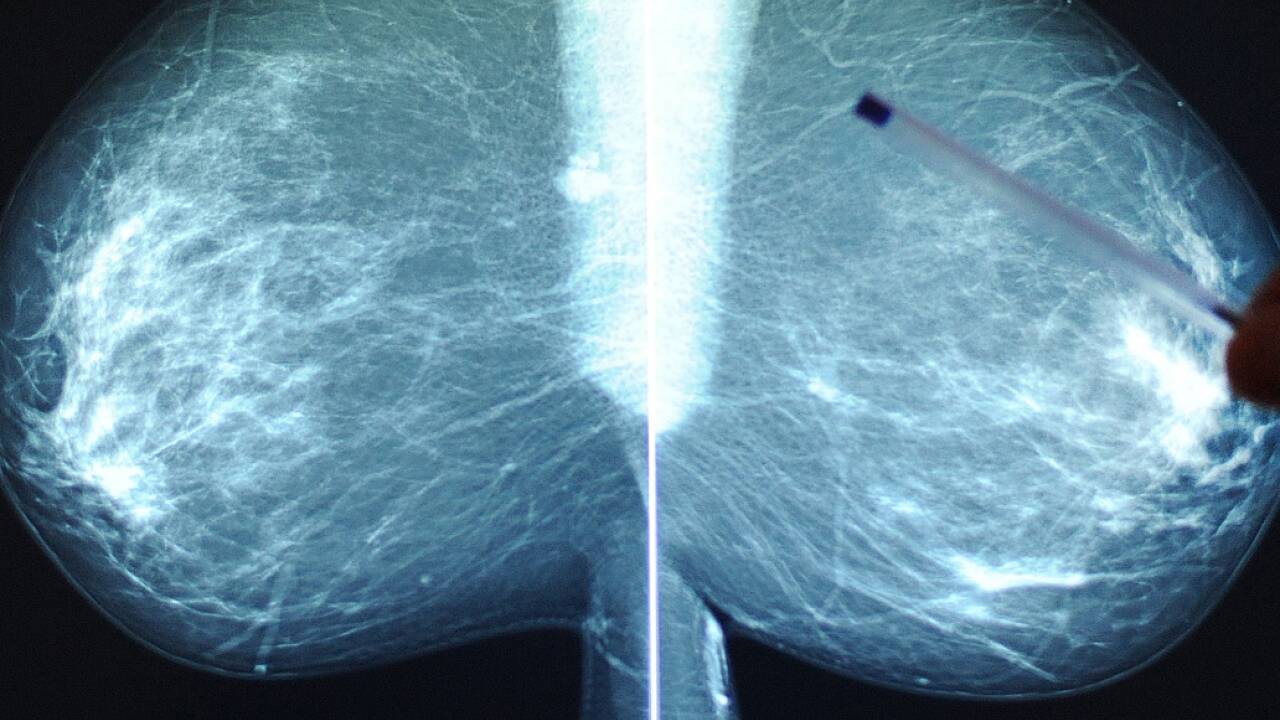

Der Lockdown hatte Auswirkungen auf die Brustkrebs-Früherkennung in Österreich. In dieser Zeit wurden 40 Prozent weniger Mammakarzinome neu diagnostiziert, weil viele Vorsorgeuntersuchungen verschoben oder abgesagt wurden.

Einiges konnte schon aufgeholt werden, aber die Zahl der Screenings liegt noch 15 Prozent unter jenen des Vorjahres, so Experten am Dienstag bei einer Pressekonferenz in Wien. "Krebs kennt keinen Lockdown!" mahnte der Leiter des Brustgesundheitszentrums der Medizinischen Universität Wien, Christian Singer. Er appellierte, Vorsorge, Diagnose, Therapie und Nachbetreuung wieder uneingeschränkt wahrzunehmen. Der Leiter der Österreichischen Gesellschaft für Senologie (ÖGS), einem interdisziplinäres Forum für Brustgesundheit, verwies in diesem Zusammenhang auf Schätzungen aus Großbritannien, die von einer substanziellen Zunahme von vermeidbaren Mortalitäten bei Krebserkrankungen ausgehen. Erste Zahlen zu Krebs im Lockdown von März bis Mai legen nahe, dass die Auswirkungen für manche Betroffenen dramatisch sein können. Dies betrifft zum Beispiel Brustkrebs in gut behandelbaren Frühstadien.

Aktuell laufen statistische, österreichweite Erhebungen der Fachgruppe Radiologie der Österreichischen Ärztekammer. Erste Ergebnisse legen nahe, dass die Frequenz an Screeninguntersuchungen im März und April um 70 bis 80 Prozent zurückgegangen sind. Vor allem die asymptomatischen, sogenannten "screen-dedected" frühen Krebsstadien wurden also in dieser Zeit nicht diagnostiziert. "In der Zwischenzeit konnten die Untersuchungen teilweise nachgeholt werden. Wir liegen aber derzeit noch immer 15 Prozent unter den Zahlen des Vorjahres".